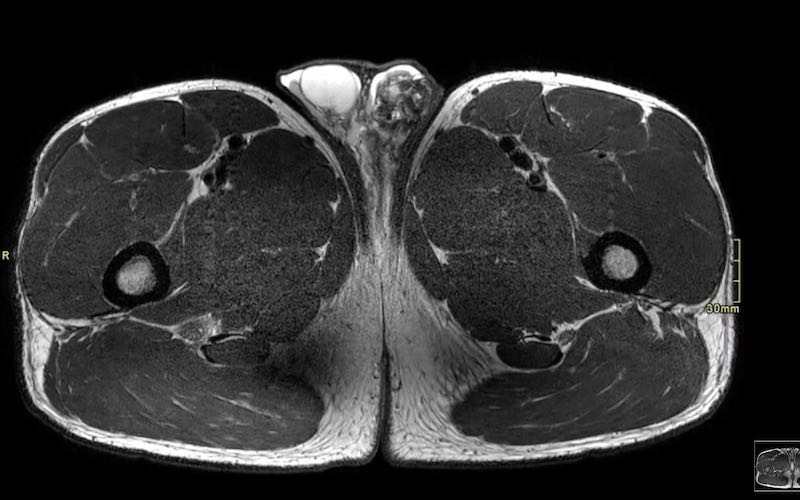

Tốt nhất nên xác định gân nào bị rách trên các ảnh axial.

Củ ngồi có thể được hình dung như một chiếc ốc quế kem, với gân cơ bán màng (anterolateral – trước ngoài) và gân chung (posteromedial – sau trong) như hai viên kem với hương vị StracciatelLa CaraMel.

Hình ảnh cho thấy bong gân cơ bán màng.

① Gân cơ bán màng

② Gân chung

Ghi nhớ các hương vị:

Stracciatella – Semimembranosus (cơ bán màng) ngoài

Caramel – Conjoint (gân chung) trong

Ở bệnh nhân này, cả gân cơ bán màng bên phải lẫn gân chung đều bị bong.

Cả hai viên kem đều đã rơi.

Trên các hình ảnh này ghi nhận tổn thương toàn bộ chiều dày.

Cả hai viên kem đều rơi trên ảnh axial, cho thấy cả hai gân đều bị bong.